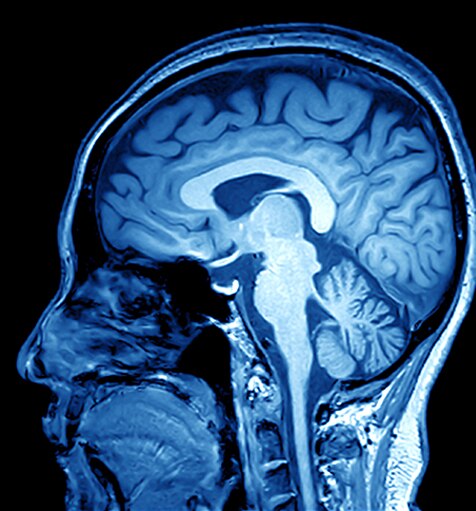

L’MRI (risonanza magnetica per immagini) è una tecnologia di scansione non invasiva che produce immagini del corpo elaborate in sezione trasversale. Viene utilizzata in diversi ambiti medici, tra cui: diagnosi muscoloscheletriche, gastrointestinali, oncologiche, cardiovascolari e neuroimaging. La scansione MRI è in grado di differenziare le strutture dei tessuti molli su qualsiasi piano, rivelandosi un prezioso strumento diagnostico.

Gli scanner per MRI generano un forte campo magnetico che, utilizzato in combinazione con la corrente a radiofrequenza, stimola molecole specifiche del corpo.

Il comportamento di tali molecole consente di generare un’immagine tridimensionale dei tessuti corporei. Di seguito sono mostrate alcune immagini ottenute con MRI: